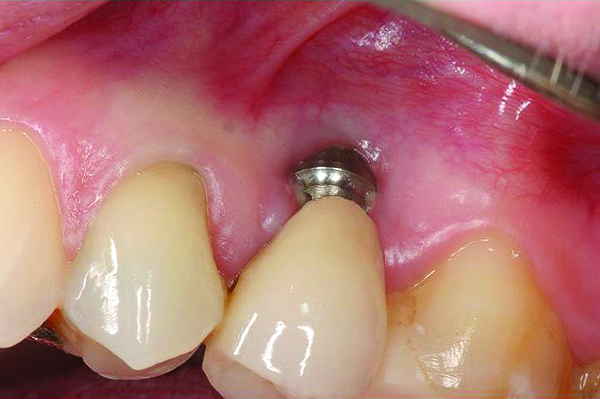

A implant restoration with a buccal dehiscence of bone and soft tissue caused by poor implant positioning, lack of keratinized tissue prior to implant placement, and soft tissue recession post implant restoration.

Figure 8

The implant of the patient shown in Figure 8 demonstrated all three of the red flag situations: it was placed too far buccally, had inadequate bone and soft tissue at the time of implant placement, and lost bone and soft tissue post implant placement. Correcting this required increased time, cost, and surgeries (Figure 9).